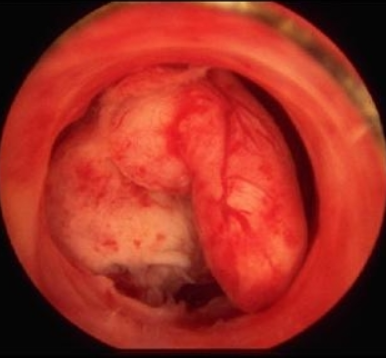

| ▲ 자궁암 근종. |

자궁암은 자궁경부암으로 즉 자궁 입구에 생기는 암을 말한다. 자궁경부암은 거의 대부분 자궁경부를 싸고 있는 상피세포에 생기게 되는데 대부분 성관계를 통해 전염이 되며 피부접촉으로도 전염될 수 있다.

자궁경부암은 전암 단계에서는 아무런 증상이 없어 진행이 되는지 모르는 사람들이 대부분이며 초기의 경우 가장 흔한 증상으로는 질 출혈, 성교접촉시의 출혈, 비정상적인 질 분비물 이런 증상들이 나오게 된다. 자궁경부암 말기 암 환자의 경우 방광이나 직장 등 주위 조직으로 침범돼 배뇨, 배변장애가 오고 하복부 통증, 요통, 하지통 등의 증상이 나타난다.